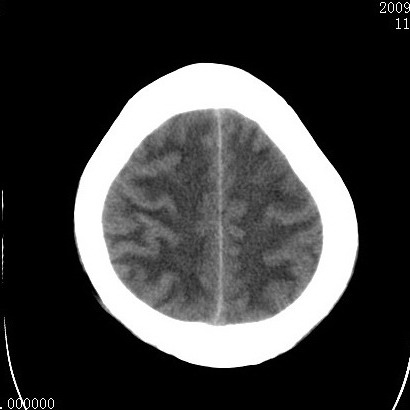

以下是引用余辉在2009-4-9 17:34:00的发言:[br]双侧脑白质对称性弥漫性密度减低,脑室脑沟裂池变小,双侧豆状核对称低密度,脑干对称性低密度,考虑1中毒性脑病2电解质异常(低钾钠等)3代谢异常及维缺乏等,进一步检查。